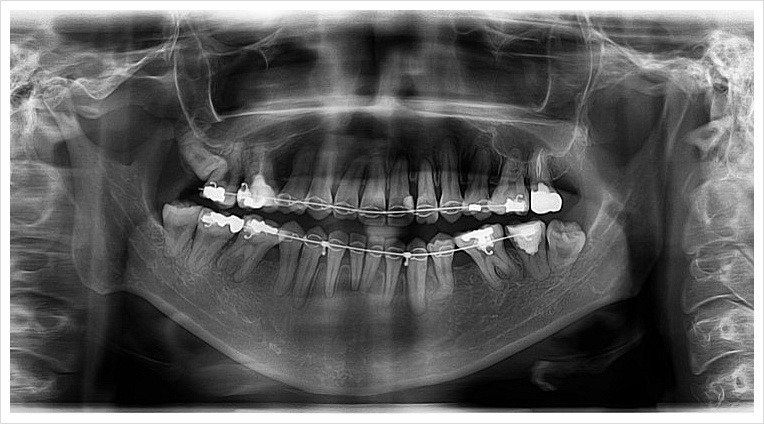

양악수술은 여러 단계로 이루어집니다. 먼저, 환자의 상태를 진단하기 위해 X-ray 촬영과 3D 스캔을 진행합니다. 이후, 수술 계획을 세우고, 수술 당일에는 전신 마취를 시행합니다. 수술 과정은 상악과 하악의 뼈를 절단하고, 필요한 위치로 이동시킨 후 고정하는 방식으로 진행됩니다. 수술 시간은 보통 1~7시간 정도 소요됩니다.

| 양악수술 전 (정면) | 양악수술 후 (정면) |